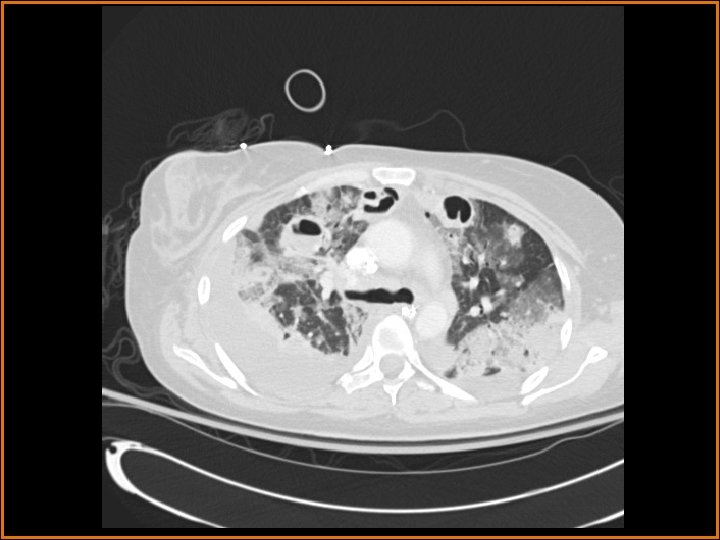

Findings and Differentials CT Findings: Multiple bilateral peripheral nodular opacities are seen, many of which are fed by arterial branches. Some of the nodules are cavitary. Diffuse bilateral ground glass opacities are seen with air bronchograms. The large lucency projecting over the right hemidiaphragm on the plain film corresponds to a pleural air collection that is directly contiguous with one of the cavities. Differential Diagnosis: • Multiple cavitary metastases • Septic Emboli

Discussion The differential diagnosis of cavitary nodules includes cavitary metastases, septic emboli, fungal infections, rheumatoid nodules, Wegener's granulomatosis, and rheumatoid nodules, among others. In this patient with fever, an infectious or inflammatory etiology is at the top of the differential. Correlation of the history with the imaging findings supports the diagnosis of septic emboli. Septic emboli usually manifest as multiple, bilateral peripheral opacities which may or may not cavitate. Often, the emboli will be in different stages of cavitation. Demonstration of a feeding vessel into the nodules indicates the hematogenous etiology of this process (although hematogenous metastases and a small-vessel vasculitis could certainly exhibit this feature also). Septic emboli may lead to pulmonary infarctions, which are seen as wedge-shaped opacities abutting the pleural surface, with the apex of the triangle pointing away from the pleura. The periphery of the infarct can enhance, but the center usually does not. Distinguishing infarcts from pneumonia is made easier when a vessel can be seen terminating at the apex of the infarcted region. (CONTINUED ON NEXT SLIDE)

Discussion (Continued) In this patient, the large right anteroinferior pleural air collection is contiguous with one of the cavities (as seen on the second CT image) and represents a bronchopleural fistula. Etiologies of bronchopleural fistulas include necrotizing infection, active TB, irradiation, tumor in a bronchial margin, etc. If the bronchopleural fistula is large, a persistent pneumothorax with or without contralateral mediastinal shift may be present. In this case, a septic embolus had eroded into the pleural space, creating the lucent collection projecting over the right hemithorax on the plain films. Finally, the ground glass opacities represented pneumonia in this patient.